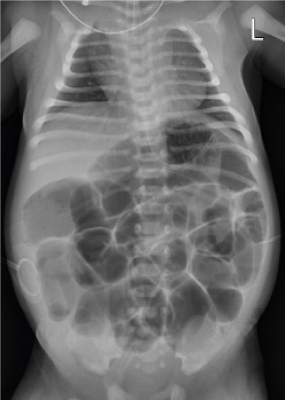

On the second day of life, abdominal distension was aggravated, and the patient was unable to pass meconium without rectal irrigation. Simple radiographs showed generalized bowel dilation, which had worsened from the previous day (Fig. 1). As the symptoms did not improve, a barium contrast enema was administered on the 4th day of life, and we checked for suspicious lesions in the transition zone of the descending colon (Fig. 2A). Warm saline irrigation was performed daily, but the abdominal distension became more severe. The patient subsequently developed a fever, and blood tests revealed an increase in C-reactive protein (CRP). Since there was no change in other findings other than the abdominal symptoms, the fever was determined to be due to an abdominal problem. The patient started taking antibiotics and we decided to skip a rectal biopsy and proceed immediately with surgery. Loop ileostomy with incidental appendectomy was performed on the 7th day of life. First, appendix resection was performed, and as a result of frozen section biopsy, it was confirmed that there were no ganglion cells. An ileostomy was performed approximately 25 cm above the ileocecal valve, and frozen section biopsy was performed at the stoma site. Some cells from the biopsy resembled ganglion cells, but they were found to require further examination. After surgery, the patient was able to pass gas and defecate through the stoma. Permanent biopsy results confirmed that the absence of ganglion cells was noted upon biopsy of the appendix and stoma site, but immunohistochemistry of calretinin and neurofilaments yielded negative results (Fig. 2B).

Fig. 1

Simple radiograph showing marked distension of the bowel.